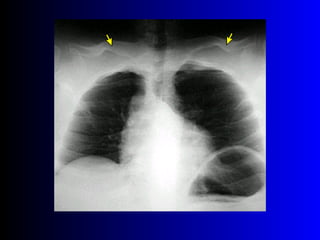

Este documento describe la técnica para realizar una telerradiografía de tórax normal e identifica las estructuras visibles en la imagen, incluyendo los huesos, vasos sanguíneos, grasa, tejido subcutáneo, pulmones y mediastino. Explica que es importante centrar la imagen en los ápices pulmonares, senos costodiafragmáticos e inspiración profunda para una visión clara de las estructuras.